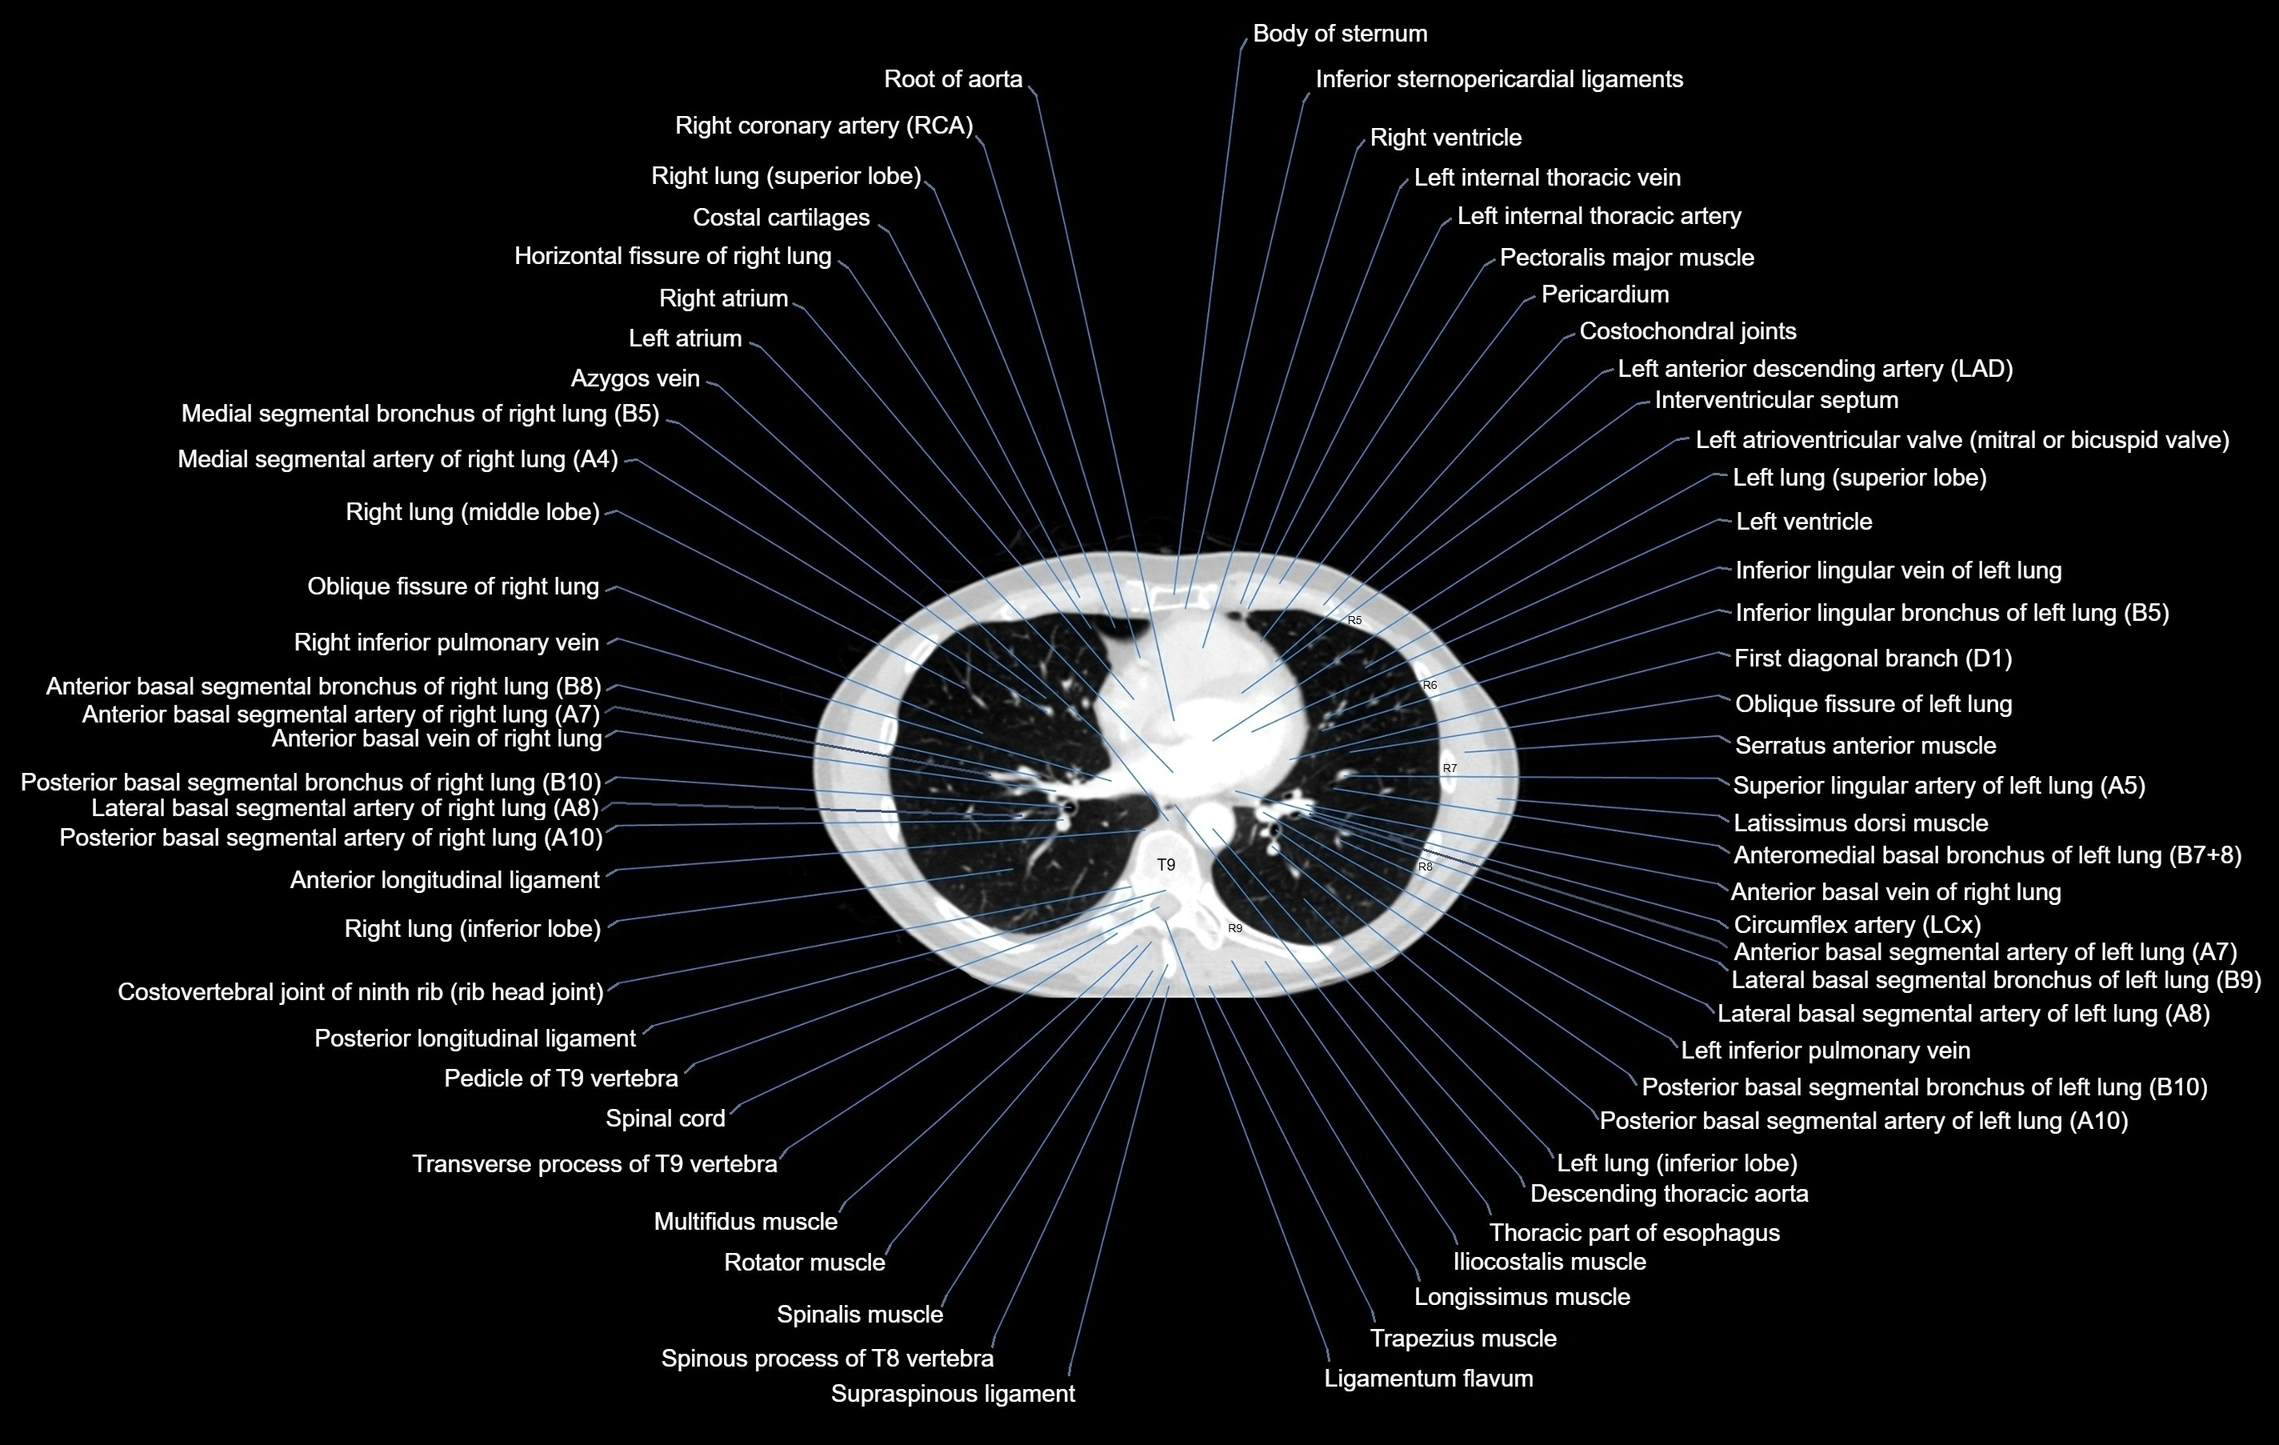

CT images